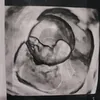

Asmirandah dan Jonas Rivanno sedang dilanda kesedihan. Anak kedua mereka yang berada di dalam kandungan dinyatakan bahwa jantungnya sudah tak berdetak. Asmirandah harus menerima kenyataan bahwa dirinya alami keguguran di usia kehamilan 9 minggu.

Awalnya, Jonas Rivanno dan Istrinya terserang Covid-19. Saat itu, usia kehamilan Asmirandah mencapai 7 minggu.